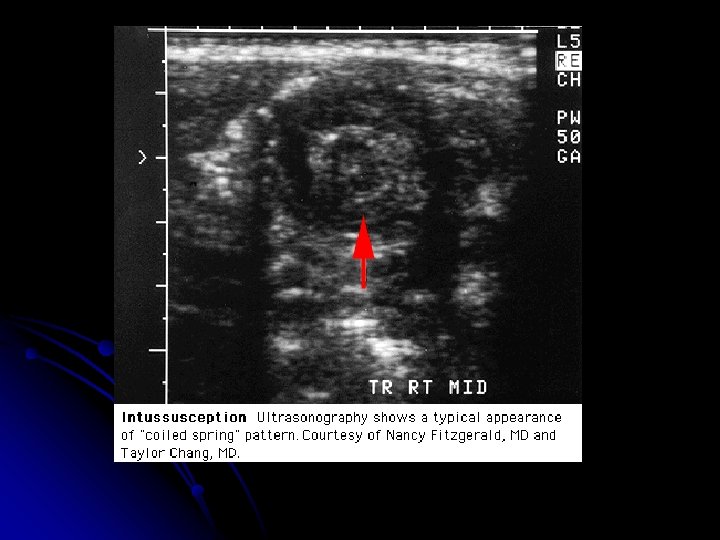

Diagnosis & Treatment l Abdominal plain films: l Crescent sign l Target sign l Ultrasonography: l Bull’s eye sign l Coiled spring sing l Target sign l CT scan (3 -1)